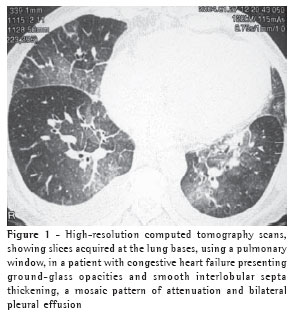

The thickening of the interlobular septa was bilateral in thirteen cases (Figures 1-4) and unilateral in two, also in the patients with fibrosing mediastinitis. In all cases, the thickening was of the smooth type.

Pleural effusion was the third most common tomographic finding overall and was the most common nonparenchymal finding, being found in 13 patients (87%), predominantly in the bilateral form (n = 11) (Figures 1-3).

Among the eleven patients with bilateral pleural effusion, nine presented asymmetric pleural effusion, predominantly on the right side. Two cases of exclusively right-sided pleural effusion were identified.

Vascular diameter was increased in seven cases (44%) (Figure 3).

On high-resolution computed tomography scans, increased diameter of arteries and veins can be seen, facilitating their recognition in the perihilar regions, in which arterial diameter is usually similar to that of the respective bronchi.(3,9)

In the present study, an increase in vascular diameter was identified in seven patients (47%). Some authors(3) consider increased vascular diameter an early finding for hydrostatic edema in the evaluation of chest X-rays. Its characterization is nevertheless difficult. Tomography allows vascular diameter to be measured in a more straightforward manner, comparing the diameter of the vessels with that of the corresponding bronchi. Other authors(9) have also observed an increase in vascular diameter in four of seven hydrostatic edema patients.